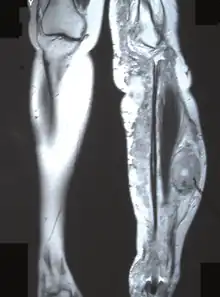

Solitary malignant peripheral nerve sheath tumor.

Diagnostic imaging MPNST

The most conclusive test for a patient with a potential neurofibrosarcoma is a tumor biopsy (taking a sample of cells directly from the tumor itself). MRIs, X-rays, CT scans, and bone scans can aid in locating a tumor and/or possible metastasis.